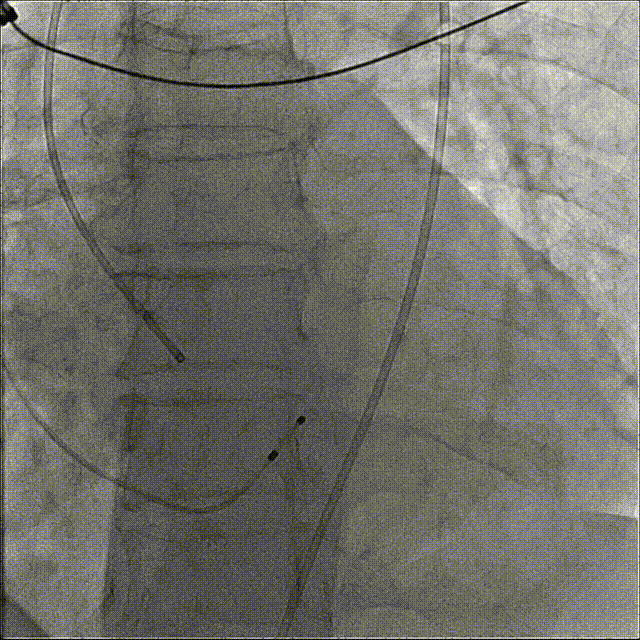

主动脉根部造影

过弓

定位造影